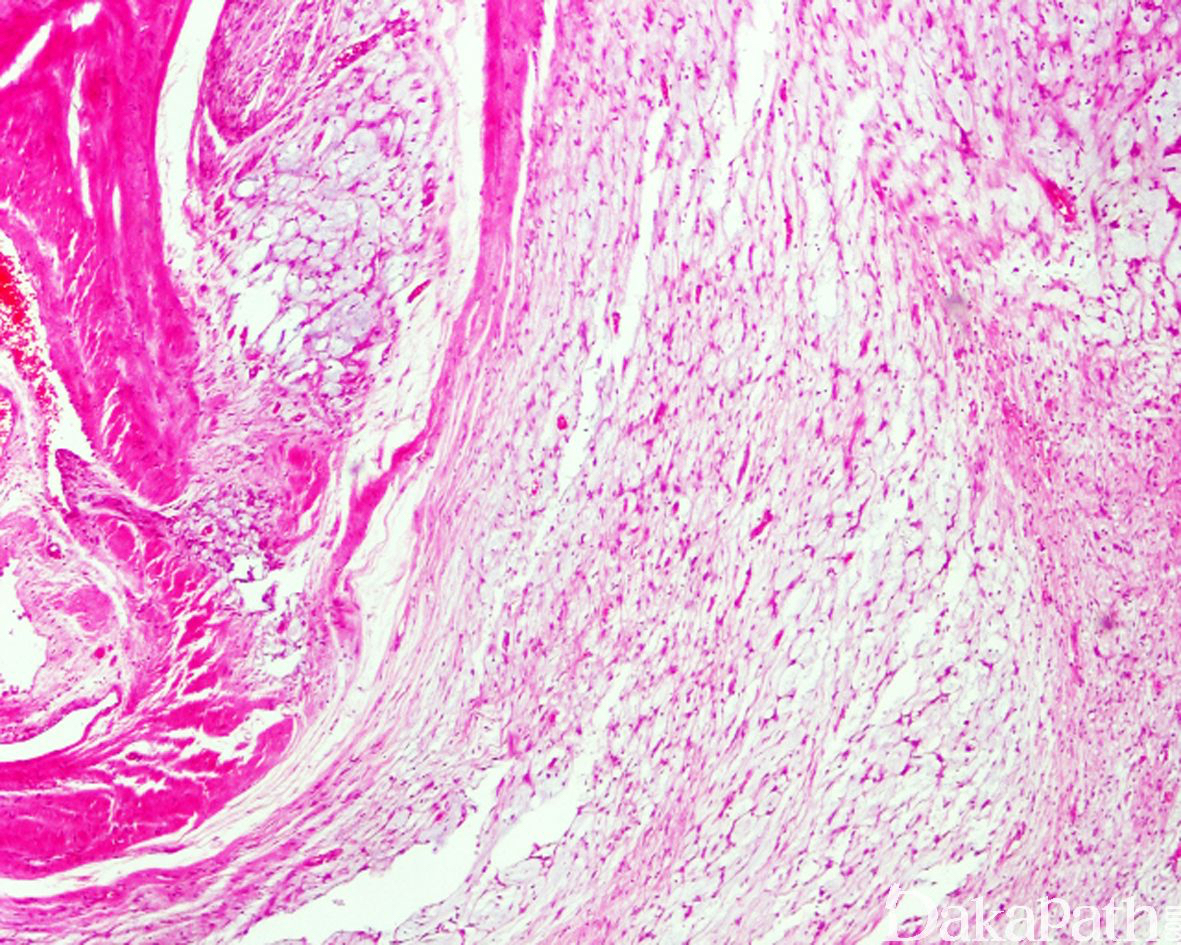

微囊/网状型神经鞘瘤

Microcystic / reticular schwannoma

大部分或完全由位于黏液性基质内的微囊和/或网状结构组成的一种少见组织学类型的神经鞘瘤

发病部位: 全身各部位均可发生,80%发生于深部软组织或内脏器官,约 50%发生于胃肠道